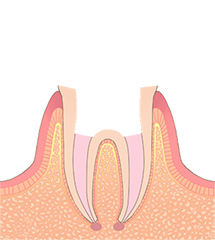

C2中等度う蝕

エナメル質が完全に溶け、象牙質という歯の中層が虫歯になった状態です。冷たいものがしみる、風が当たると痛い、などの症状が現れ、治療が必要な状態です。小さければ、白いプラスチックで埋めることもできますが、大きくなると、型取りが必要になります。